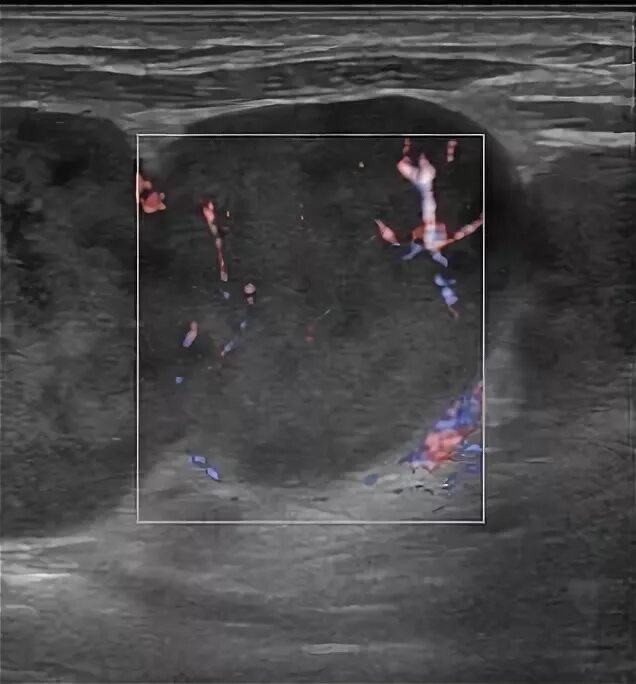

Метастазы в лимфоузлах форум